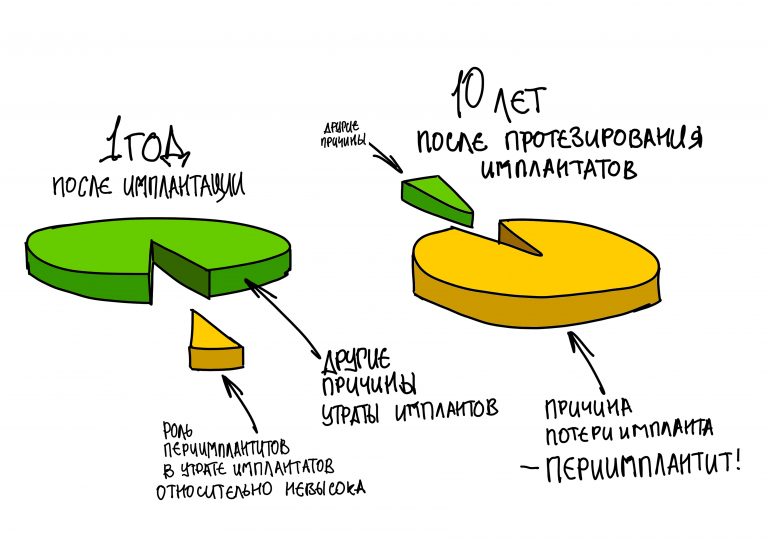

Периимплантит сам по себе не является показанием к удалению имплантатов. Он лечится, причем весьма успешно — но ровно до того момента, пока его лечения целесообразно с точки зрения медицины и финансов. Вместе с тем, перимплантит является причиной утраты интегрированных имплантатов в 99% случаев — когда пациент своим бездействием доводит клиническую ситуацию до катастрофы.

Как я отметил выше, 99% утрат уже интегрированных и протезированных имплантатов происходит именно по причине запущенного периимплантита, когда его лечение становится нецелесообразным.

— вот эта ваша статистика про 99.8% результативности дентальной имплантации, которой любят козырять как производители имплантатов, так и доктора с клиниками, указана для случаев, когда пациент действительно соблюдает все вышеуказанные правила, а стоматолог не теряет контроль над развитием и изменениями клинической ситуации. Иначе, откуда же этой статистике взяться?